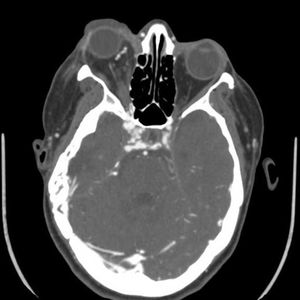

Case history: A 74-year-old male complaining of from difficulty swallowing, fever and neck pain.